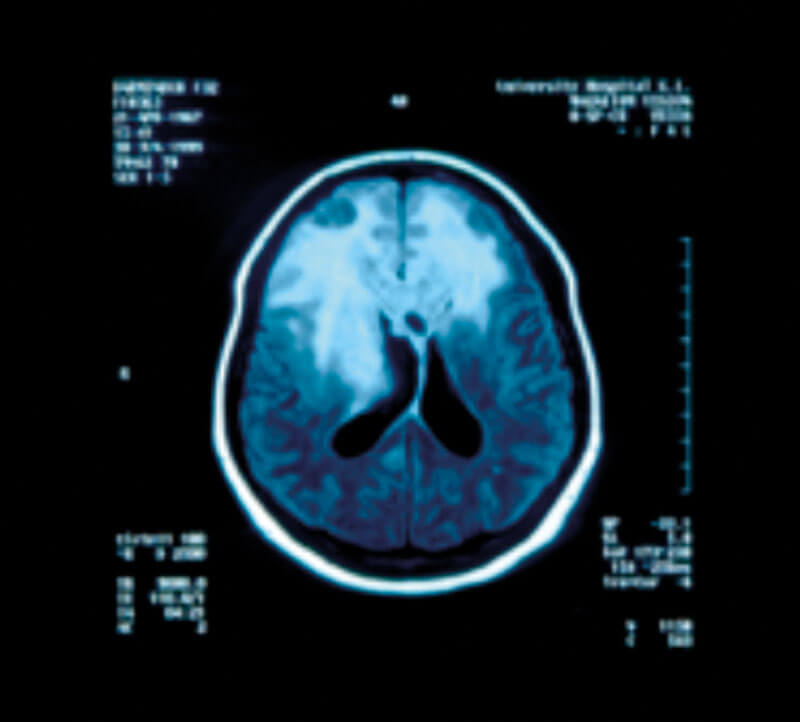

Figure 5: Pathology of an infiltrating glioblastoma with extensive haemorrhage.

Astrocytomas comprise up to 50% of primary brain tumours and can originate anywhere in the brain parenchyma, often presenting with seizures; the more benign varieties are commonest in the fourth decade of life but the GBM is usually seen in the fifth or sixth decade (Figures 4 and 5).